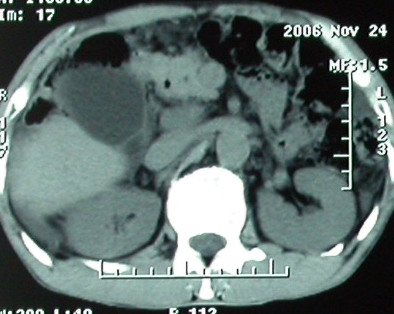

作者: rsyby 时间: 2006-11-28 22:53

增强ct所见

影像表现:胆囊扩张、肝内胆管不扩张,且见肝脏内树枝样气体影;十二指肠后方等密度占位,中心有不规则囊变区。增强实质部分轻度强化。下部腔静脉未强化------有栓子吗?

1、胰头部占位:胰管轻度扩张(可疑双管征),主要考虑恶性肿瘤,胰头癌?十二指肠间质瘤?后腹膜肿瘤?

2、门静脉高压症,主要考虑胰头部肿块压迫或者浸润所致肝前性门静脉主干受压;肝功能尚可,脾脏不大,无脾亢;

3、胆囊积液、肝胆管积气、胆道扩张伴有胆道感染;

4、右肝后上段占位(考虑肝胆管结石伴肝组织萎缩?)

5、下腔静脉受压;

6、左半肝缺失,原因不明?

手术结果:

肝脏尾状叶肝癌(沿肝十二指肠韧带向下韧带内生长,门腔间隙外压增大),大结节性肝硬化,胆囊积脓,胆道感染。术中见肝外胆道2cm直径,肿瘤向前压迫胆管至扁平状态。